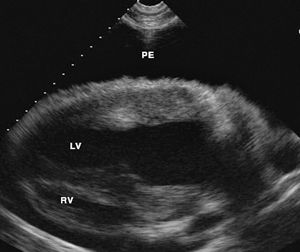

Pericarditis is an inflammatory condition of the pericardial lining of the heart. It is characterized by accumulation of fluid, fibrin or fibrous tissue within the pericardial sac. Pericarditis is seen more commonly in young horses.1,2 There is no breed predilection. Male intact horses may be at increased risk.1